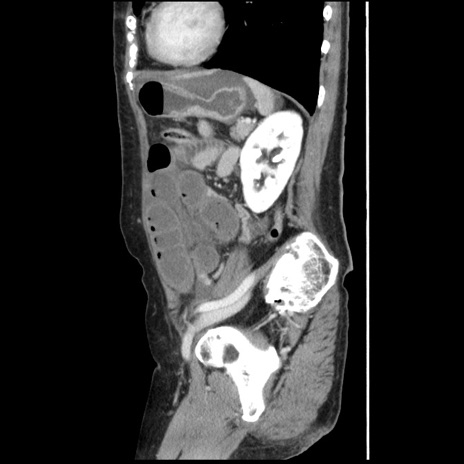

症例1(矢状断像)

【症例】80歳代女性

【主訴】腹痛

【現病歴】8時間前から腹痛あり来院。

【既往歴】糖尿病、脂質異常症、子宮体癌にて子宮全摘術

【身体所見】意識清明・会話良好だが腹痛で苦悶様、全腹部にわたって反跳痛と圧痛あり

【データ】WBC 13600、CRP 0.14、LDH 224、CK 90